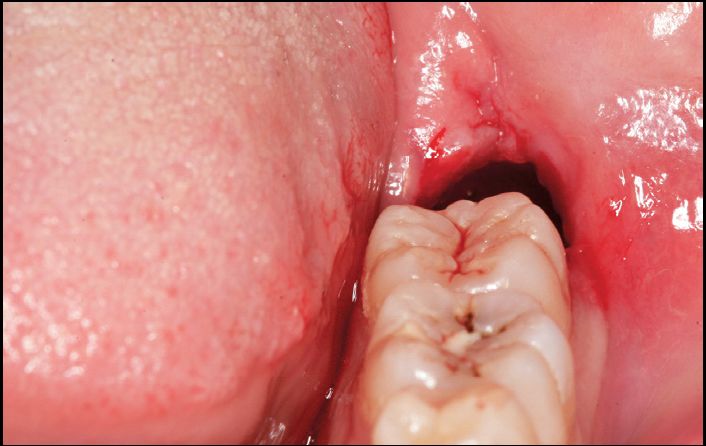

A.水平智齿仅露出远中牙冠

B.X线显示阻生智齿水平中位

C.直接分牙法并未切开、翻瓣、去骨拔除

D.智齿拔除,牙槽窝完好